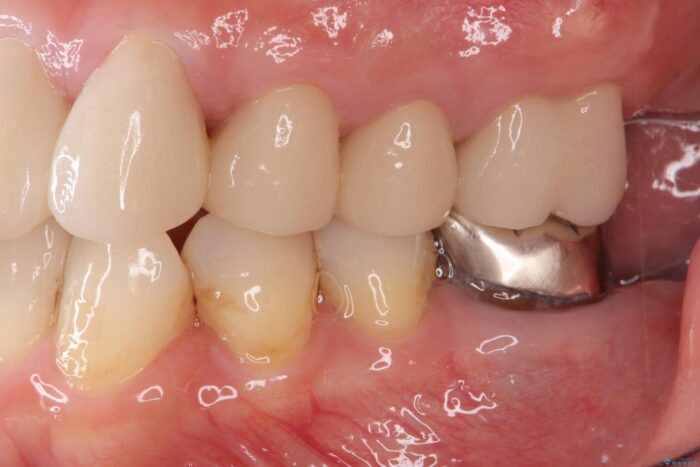

セラミッククラウンの治療は、天然の歯のような審美性を回復できることも大切ですが、精度が高くきっちりと歯ブラシを行いやすい状態を整えることで虫歯や歯周病の再発リスクを下げることも非常に大切です。